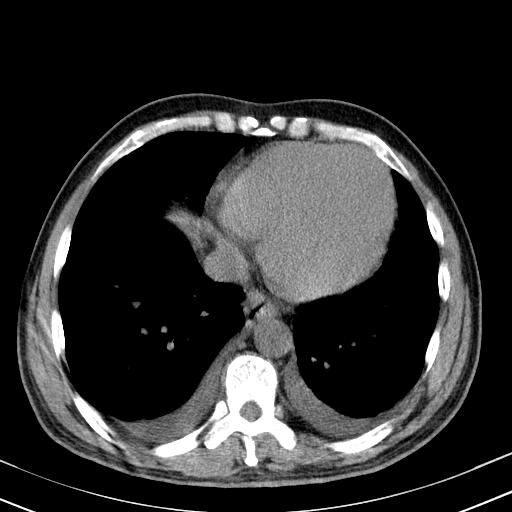

以下是引用zxl51642在2010-3-21 17:06:00的发言:[br]右下中心型肺癌并阻塞性肺炎/不张,纵膈淋巴结肿大,右侧大量胸腔积液,左侧少量胸腔积液,少量腹水。建议纤维支气管镜进一步检查。